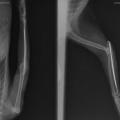

Kass on opereeritud! - Кошка прооперирована.

Диагноз:

- вывих локтевого сустава

- перелом локтевой кости

- межмыщелковый перелом плеча(?)